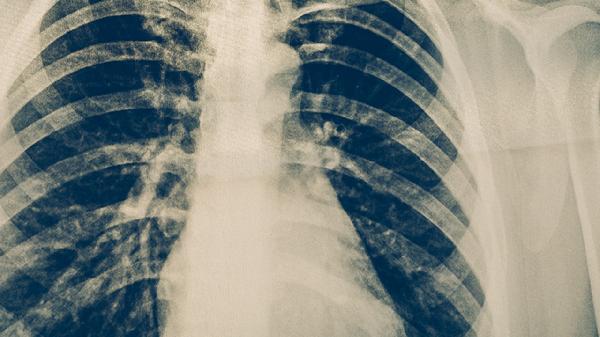

高危人群每1-2年进行胸部X线检查,接触者需做结核菌素试验或γ-干扰素释放试验。出现持续咳嗽、低热、盗汗等症状时应及时就诊,早期发现可通过异烟肼片、利福平胶囊等药物进行预防性治疗。